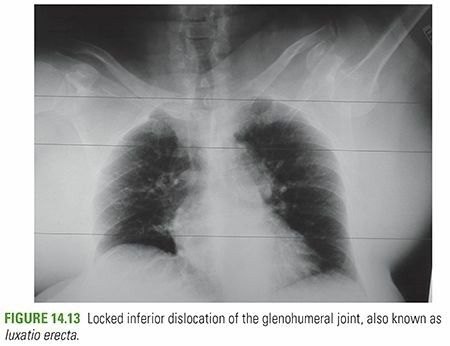

INFERIOR GLENOHUMERAL DISLOCATION (LUXATIO ERECTA) This very rare injury is more common in elderly individual…